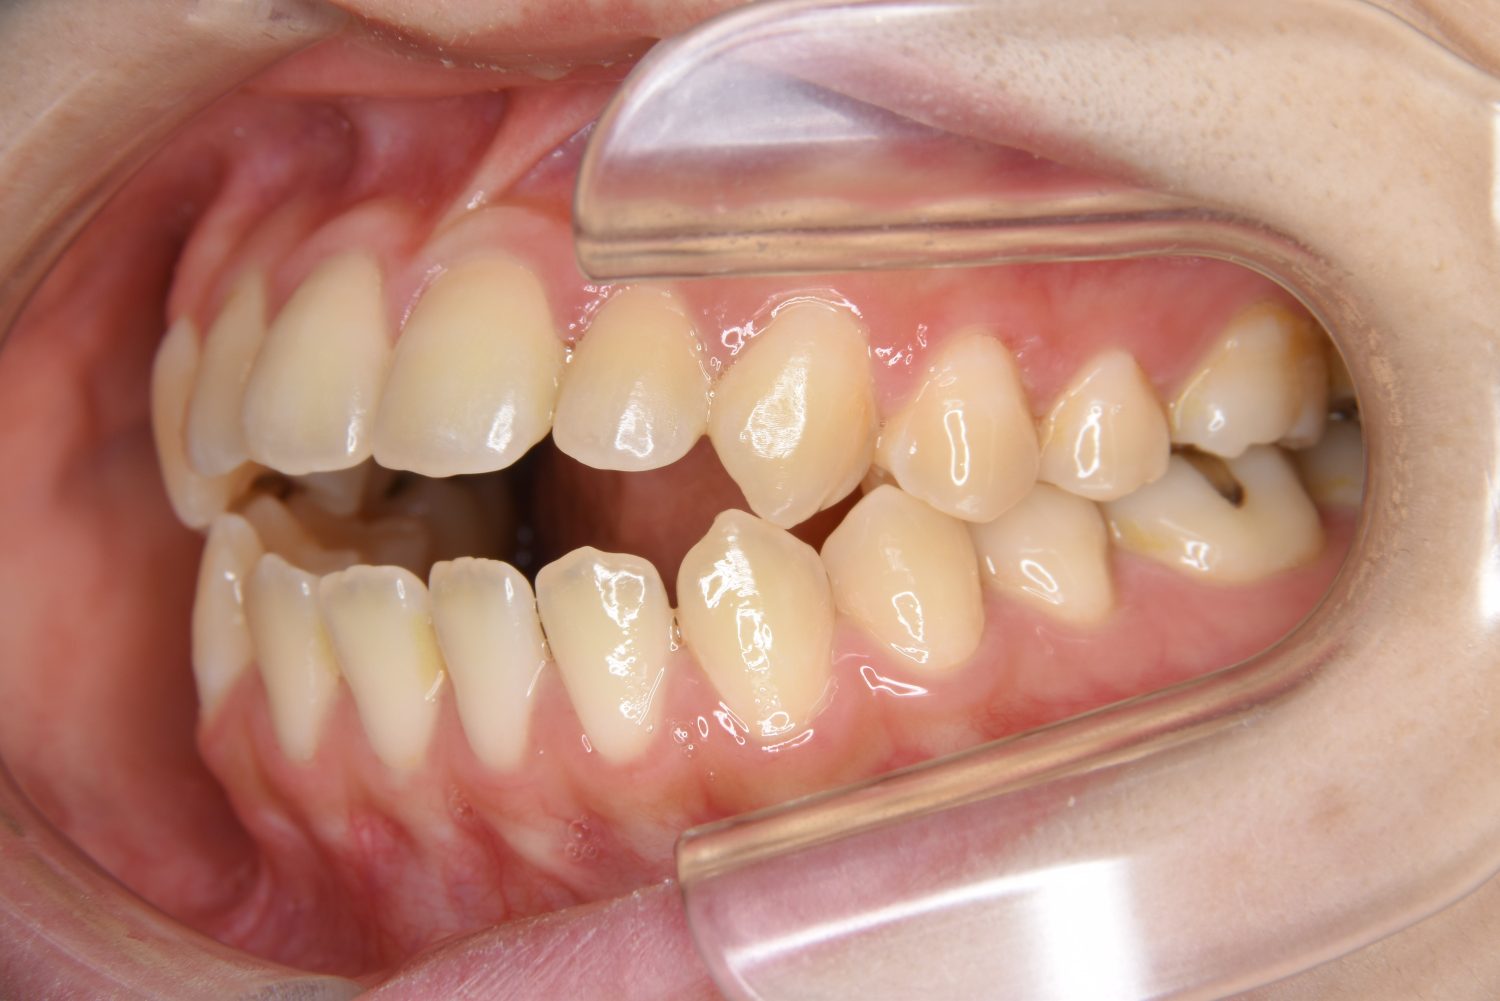

前歯部開咬の症例紹介①

Before

主訴

前歯が開いているのが気になる。

治療内容

上リンガルブラケット(舌側装置)、下ラビアルブラケット(唇側装置)に矯正用アンカースクリューを併用し非抜歯で治療を行いました。

上下の前歯が開いており前歯では全く噛めていない状態でした。臼歯の圧下を行うことで前歯でも咬合できるようになり機能面のみでなく審美面も著しく改善しました。